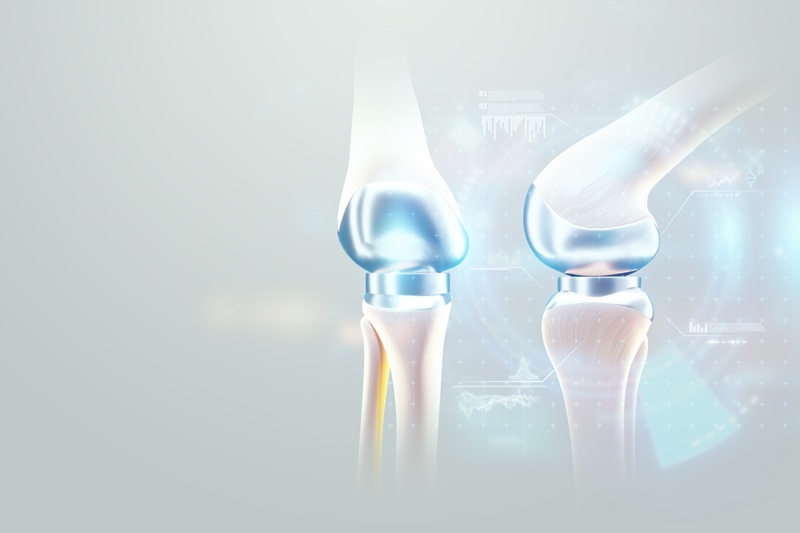

Prótesis de rodilla y cadera

Reemplazo articular con planeación personalizada y técnicas mínimamente invasivas para aliviar dolor y recuperar movilidad. Incluye selección de implante, control de riesgos y rehabilitación guiada integral.

Cirugía artroscópica de rodilla

Resolución de lesiones meniscales, de cartílago y ligamentos mediante artroscopia. Incisiones pequeñas, menor dolor y recuperación acelerada. Diagnóstico preciso, estabilidad funcional y retorno progresivo.

Cirugía asistida por robot

Planeación 3D y ejecución precisa para reemplazos e intervenciones complejas. Menor sangrado, alineación óptima y resultados predecibles. Mayor seguridad quirúrgica y recuperación fiable con control intraoperatorio.